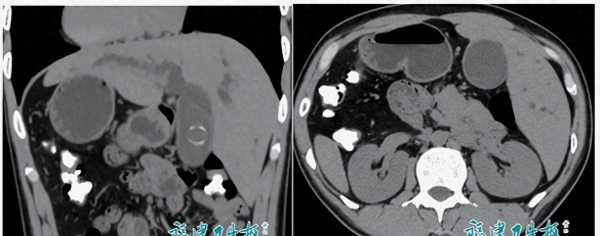

检查结果把大家的注意力一下拉满:右位心、完全性内脏反位,再加上胆总管结石。

CT片子翻出来,标注的心脏阴影在右边,肝脏在左边,胆管也"对调",影像像照镜子一样,"反"的细节在每一帧都看得清清楚楚。